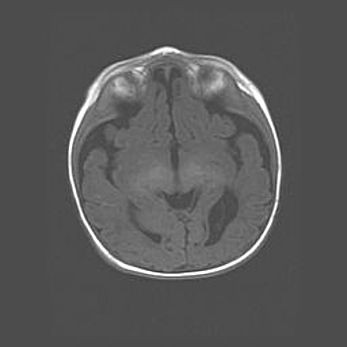

Мальформация Денди-Уокера. Киста задней черепной ямки.

Агенезия мозолистого тела.

Возраст: 2,5 месяца

Вес: 2420 г

Пол: женский

Окружность головы: 37 см

Срок гестации: 32 недели

Мальформация Денди—Уокера — редкий вид патологии ЦНС, представляющий собой врожденный порок развития каудального отдела ствола и червя мозжечка, ведущий к неполному раскрытию срединной (Мажанди) и латеральных (Лушка) апертур IV желудочка мозга. Для этогно синдрома характерна триада симптомов: гипотрофия червя мозжечка и/или полушарий мозжечка, кисты задней черепной ямки, гидроцефалия различной степени. В 70% случаев порок сочетается и с другими аномалиями головного мозга, в частности с агенезией мозолистого тела.